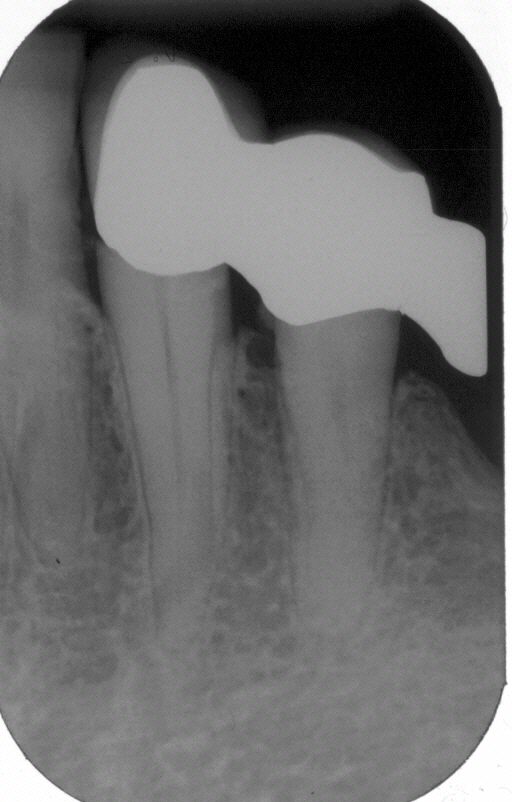

Wurzelfüllung

Wurzelfüllung in lateraler Kondensation mit genormter Guttapercha und AH 26 im Juli 2002